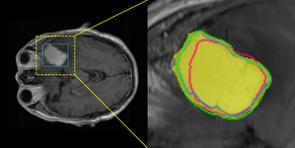

Accurate magnetic resonance imaging (MRI) segmentation is crucial for clinical decision-making, but remains labor-intensive when performed manually. Convolutional neural network (CNN)-based methods can be accurate and efficient, but often generalize poorly to MRI's variable contrast, intensity inhomogeneity, and protocols. Although the transformer-based Segment Anything Model (SAM) has demonstrated remarkable generalizability in natural images, existing adaptations often treat MRI as another imaging modality, overlooking these modality-specific challenges. We present SAMRI, an MRI-specialized SAM trained and validated on 1.1 million labeled MR slices spanning whole-body organs and pathologies. We demonstrate that SAM can be effectively adapted to MRI by simply fine-tuning its mask decoder using a two-stage strategy, reducing training time by 94% and trainable parameters by 96% versus full-model retraining. Across diverse MRI segmentation tasks, SAMRI achieves a mean Dice of 0.87, delivering state-of-the-art accuracy across anatomical regions and robust generalization on unseen structures, particularly small and clinically important structures.